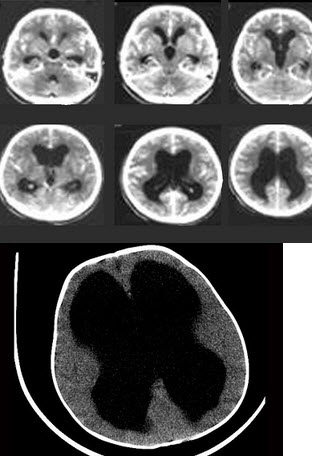

婴幼儿,女,头比一般孩子大,请结合影像图像选择最可能的诊断()

A.脑萎缩

B.阻塞性脑积水

C.交通性脑积水

D.先天发育异常

E.脑囊肿